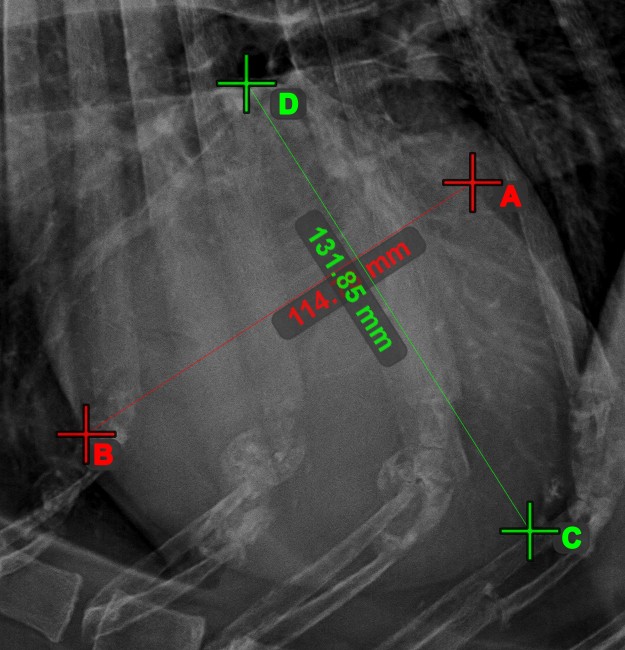

Line Measurement

Create a line measurement to calculate the distance between two points with high precision.

Select the Line Measurement tool and assign it to one of the available mouse buttons. Place the start and end points on the scene or select them from already existing points on the image. The distance between the two points will be automatically calculated by using the default calibration data, or the recalibrated data by the length calibration measurement.

Modify the start and end point by using the Select/Move Item tool. The distance between the two points will be automatically recalculated.

../_images/image164.jpg